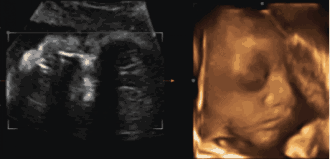

為了提前探尋這一“真相”

我們可以通過一個(gè)特別的儀式

在影像中讓寶寶與爸爸媽媽提前相遇

感受寶寶與父母奇妙的連接

這一切,只需要選擇四維彩超就可以啦